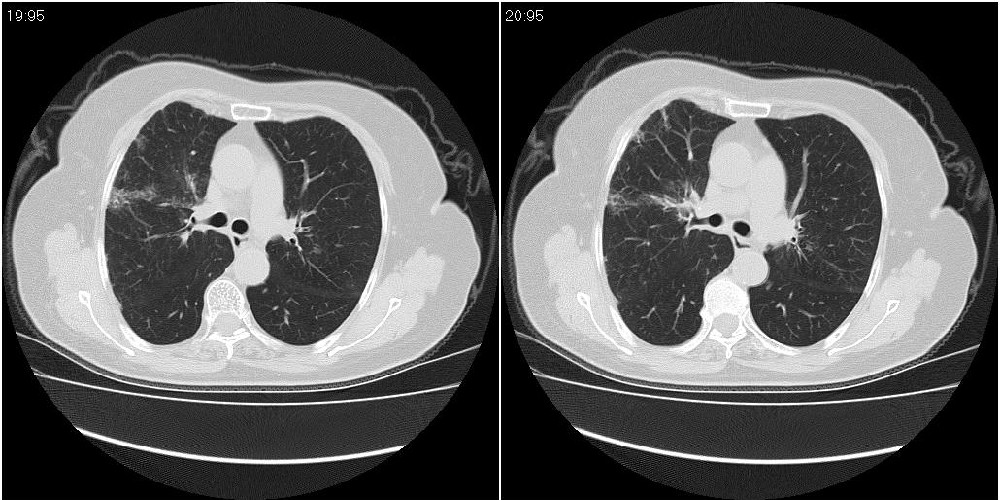

女性,72岁。去年9月份发现肺部病变,诊为肺结核并进行正规治疗至今,但复查后发现ct表现几乎没有变化。

双肺继发型tb并右中叶内膜tb,轻度支扩,左下胸膜肥厚粘连。

双肺继发性肺结核并右肺中叶节段性肺不张,左下胸膜肥厚粘连。